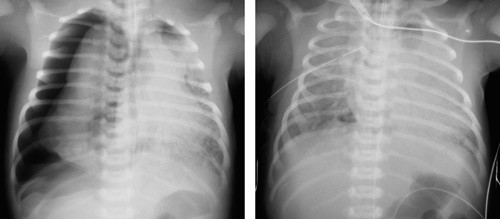

Det ble gjort en prospektiv registrering av pulmonal luftlekkasje hos barn født i perioden 1989 – 2006 og innlagt i neonatalenheten, Sykehuset i Vestfold, Tønsberg. Sykehuset hadde i den aktuelle perioden 90 % av fødslene i fylket, mens 0,7 % ble født ved regionsykehus og de resterende 9 % ved andre sentral- og lokalsykehus. Materialet er således nært populasjonsbasert. Luftlekkasje ble diagnostisert røntgenologisk ut fra pasientens sykdomsbilde (fig 1). Alle bilder ble vurdert av to radiologer, og minst én av dem, som regel begge, var spesialist i radiologi.